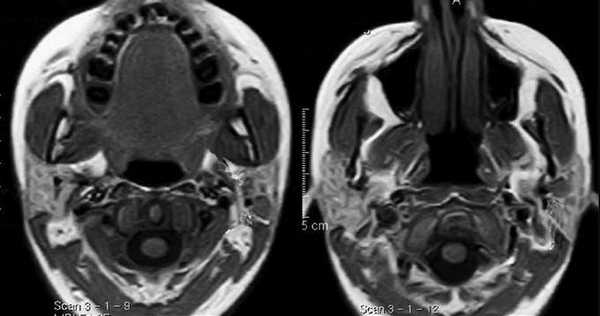

С помощью КТ сложно было выявлять опухоли малых размеров (Т1стадия) и их границы в результате низкой контрастности, а также новообразования с поверхностным распространением (рис. 1). Вместе с тем, 72,0% обследованных больных имели Т3, Т4 стадии опухолевого процесса и после болюсного введения контрастного вещества контрастность опухоли повышалась. С увеличением размера опухоли отмечалась неоднородность усиления из-за наличия некроза (рис. 2). Жировые пространства подъязычной области в нормальном состоянии представляют собой симметричную зону низкой плотности между челюстно-подъязычной и подбородочно-подъязычной мышцами. Облитерация жировых пространств подъязычной области служила основным показателем опухолевого поражения при выявлении небольших образований дна полости рта (рис. 3,4).

Сложно было выявлять опухоли малых размеров (Т1,Т2 стадии), расположенные в передних отделах дна полости рта из-за расположенных рядом костных тканей, зубов, наличия пломбировочного материала вследствие выраженных артефактов от плотных структур. В ряде случаев визуализацию облегчало наличие язвенного дефекта в структуре опухоли (рис. 5). При всех опухолях Т3, Т4 стадии определялось повышение плотности после введения контрастного вещества, их края четко визуализировались относительно окружающих тканей. Во всех случаях Т3, Т4 стадии удавалось определить размер опухоли и оценить инфильтрацию и распространение в соседние зоны, а также за среднюю линию (рис. 6).

Особенностью МРТ являлась высокая контрастность мягких тканей. Плотные костные ткани или зубоврачебный материал не создавали артефактов, что давало возможность получать четкое изображение опухоли полости рта, определять распространение в мягкие ткани, глубокие отделы орофарингеальной зоны, в область неба. На Т1-ВИ все опухоли имели ту же интенсивность сигнала, как у окружающих мышц или слабее (рис.7).

После введения контрастного вещества все опухоли показывали усиление сигнала. При локализации опухолевого процесса в области языка (12 пациентов) границы опухоли визуализировались более четко. В режиме Т2-ВИ опухолевые узлы проявлялись более высокой интенсивностью сигнала, чем у окружающих мышц (рис. 8).

Сложно было с помощью МРТ визуализировать опухоли любых размеров с поверхностным распространением, не выходящие за пределы слизистой оболочки. Опухоли малых размеров (Т1 стадия) в 2 наблюдениях были однородны, не имели центральной зоны некроза и сливались с мышцами. С увеличением размера опухолевого узла отмечалась неоднородность структуры. В наших исследованиях удалось выявить небольшие опухоли Т1 и Т2 стадий, локализованные в области языка и дна полости рта. В 9 наблюдениях опухоли Т2 стадии, не накапливающие контраст при МСКТ исследовании, хорошо визуализировались при МРТ в режимах Т2-ВИ, STIR, проявляясь сигналом высокой интенсивности. Можно было четко видеть границы опухоли и оценить ее размеры (рис. 9,10).